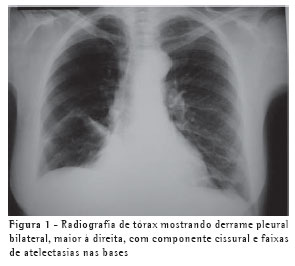

Uma mulher de 63 anos, do lar, não tabagista, previamente hígida, apresentou-se com queixa de aumento de volume em pescoço, face anterior do tórax, abdome e membros inferiores. Havia associação com dispnéia discreta aos esforços. O quadro teve início após atividade física leve em academia de ginástica, havia cinco dias. Negava doença pulmonar prévia e referia uso de fluoxetina a 20 mg/dia, bromazepam a 3 mg/dia e reposição hormonal feminina regular. Ao exame clínico observou-se um discreto aumento de volume em fossa supraclavicular esquerda e face lateral direita do pescoço. Observou-se ainda diminuição do murmúrio vesicular de forma difusa e de frêmito toracovocal em bases (direito maior que esquerdo), além de edema de parede abdominal anterior e de membros inferiores (grau I/IV). Foram solicitados hemograma, coagulograma, glicemia, creatinina, uréia, velocidade de hemossedimentação, colesterol total, HDL, triglicerídeos, T3, T4, TSH e parcial de urina, os quais se apresentaram todos normais, descartando a presença de dislipidemia, coagulopatia, infecção, nefropatia e hipotireoidismo. A avaliação radiológica do tórax revelou um pequeno derrame pleural bilateral (Figura 1), confirmado pela tomografia axial computadorizada de tórax (Figura 2A). Esta foi complementada com cortes ao nível do pescoço, que evidenciaram edema na região supraclavicular esquerda com imagem hipodensa (20 x 10 mm) adjacente ao feixe vasculonervoso do pescoço (Figura 2B). A ultra-sonografia da região cervical mostrou a formação de uma coleção cística, posteriormente aos vasos cervicais, sugestiva da ruptura do tronco jugular esquerdo. Demonstrou ainda um pequeno aumento da espessura do músculo esternocleidomastóideo esquerdo, sugestivo de processo inflamatório secundário a distensão muscular (Figura 3). A paciente foi submetida a toracocentese diagnóstica à direita com obtenção de líquido leitoso compatível com QT. A análise laboratorial demonstrou tratar-se de um exsudato com predomínio de polimorfonucleares e com dosagem de triglicerídeos de 2.035 mg/dl, colesterol de 131 mg/dl e proteínas de 9,7 g/dl, confirmando o quadro laboratorial de QT. Foram realizadas citologia oncótica, bacterioscopia de Ziehl, micológico direto e culturas, que resultaram negativos, descartando processos malignos e doenças infecciosas.